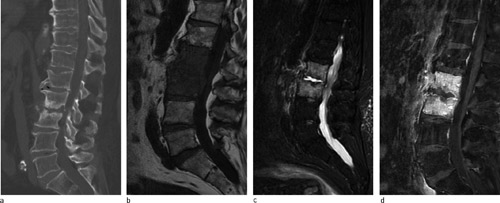

En mann i 70-årene ble lagt inn på Medisinsk avdeling med sepsis forårsaket av Streptococcus pneumoniae og ryggsmerter, tolket som lungebetennelse. Han ble initialt behandlet med intravenøs penicillin og gentamicin og utskrevet med perorale antibiotika. En uke senere ble han på ny innlagt med økende ryggsmerter, feber og stigende infeksjonsparametre. Det var ingen nevrologiske utfall. På bakgrunn av sykehistorien og sparsomme funn ved auskultasjon og røntgen thorax, ble CT columna, så MR rekvirert. CT viste uregelmessig kontur av nedre og øvre dekkplater i L2/L3, subkondrale destruksjoner og nedsatt skivehøyde (a). På standard T1-vektede (b) og STIR (short τ inversion recovery)-bilder på MR (c) ses utbredt ødem i L2, L3 og i det paravertebrale bløtvevet. På serien med kontrast med fettsuppresjon ses randkontrastoppladning i selve skiven (d). Disse funnene sammen med de kliniske funnene er forenlig med bakteriell spondylodiskitt.